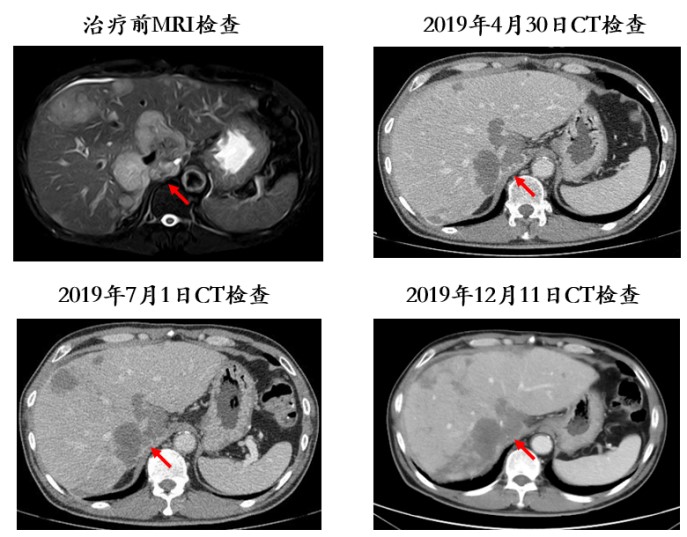

此后定期复查CT,显示门脉癌栓位于右支近汇合处,较治疗前明显退缩(图2);肿瘤灶较治疗前直径缩小,且乏血供,疗效评价为部分缓解(PR;图3)。

0.jpg

图3. 肿瘤较治疗前直径缩小,疗效评价PR